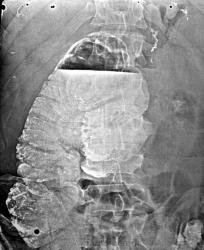

Если я окончательно не запуталась, этот случай и уровень в поперечно-ободочной кишке при контрастированной культе желудка - одно и тоже наблюдение? Правильный ответ - спаечный процесс?

Забавно, но задним числом рентгенограммы-то одного человека, по костям, по следам контраста в культе. Надо бы раньше догадаться и сопоставить, вот тогда и была бы молодец.

На операции - массивный спаечный процесс, сдавливающий толстую кишку извне.

Спаечный процесс после огнестрела? Или это множественные артефакты?

Слева, я так понимаю, была гемиколэктомия?

Глянув темы дальше стало ясно, что это множественные артефакты. Возможно, если объем опер вмешательства был несколько меньше стандартной гемиколэктомии, что делается, например, при травматических повреждениях кишки. Такая лог цепочка была вызвана мыслью об огнестреле :)

Вы не запутались - Вы молодец, Людмила Григорьевна, думаю Анатолий Владимирович будет такого же мнения

Однако, у неё выдающиеся способности к сыску. У леди Холмс-Кураевой. Но опыта пока маловато: в культе желудка следы не контраста, а п/о скрепок-швов.